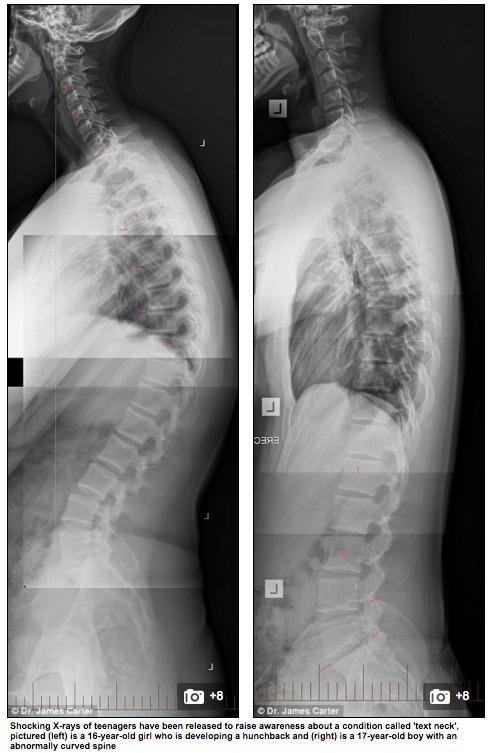

C’est un chiropracteur australien qui tire l’alarme et publie sur le site du Daily Mail Australia les radiographies de ses jeunes patients - des enfants et adolescents dont le smartphone accompagne le quotidien et bouleverse la position corporelle. Le praticien évoque une explosion des cas de pathologies osseuses liées à l’utilisation des écrans.

L’épidémie, encore silencieuse, n’est pas invisible. Un coup d’œil aux clichés radiologiques suffit pour s’en persuader. La maladie frappe les plus jeunes - la moitié des patients de James Carter vont à l’école. Elle s’accompagne d’anxiété et de symptômes dépressifs, et peut générer des dommages irréversibles et permanents de la colonne vertébrale.

Sur le cliché de droite, on aperçoit l’ossature d’une jeune fille de 16 ans. Selon le médecin, elle est en train de développer une malformation dorsale et risque de devenir bossue. Le cliché de droite appartient à un adolescent de 17 ans, qui présente une courbure anormale de la colonne vertébrale.

« Au lieu d’avoir une courbure normale, vers l’avant, on constate chez ces patients une courbure vers l’arrière, explique James Carter. Cet état provoque souvent des douleurs au cou, aux épaules et au dos. Beaucoup de patients consultent pour des maux de tête, mais on réalise très vite qu’il s’agit d’un cas de ‘cou du texto’ »